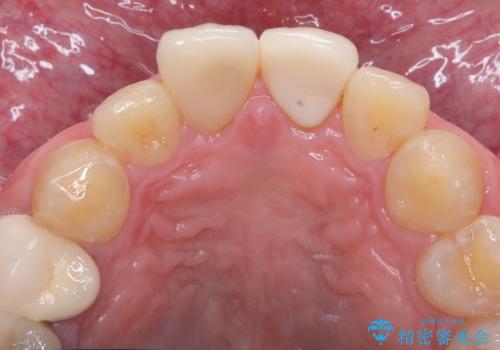

前歯の根のところに違和感がある|根尖性歯周炎|精密根管治療|オールセラミッククラウン|見た目も改善

- 前歯の違和感を主訴にご来院された患者様です。

根尖性歯周炎に罹患し根の先に膿が溜まっているのが原因でした。

精密根管治療後、オールセラミッククラウンで治療を行いました。

- 39.6万円(精密根管治療イニシャルケース11万円+ファイバーコア2.2万円+仮歯1.1万円×2+オールセラミッククラウンスタンダード12.1万円×2)費用は治療当時の料金となります

精密根管治療では、菌を入れない環境を作り見逃しが無いようにマイクロスコープを使って治療する事が大切です。

まだ誰も触っていない根管ならばほとんどのケースで治せる事が出来ます。